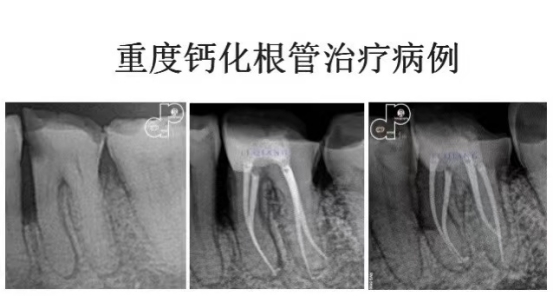

手动锉的探查与疏通 根管长度与根管预备长度的确定 根管预备的宽度确定 根管预备的逐步后退法 根管预备的冠向下法 弯曲根管的预备方法 根管化学预备的常用药物及浓度 化学预备的器械与药物使用步骤 实操:在透明模块和离体牙上实操镍钛锉根管预备

常用根管封药及选择 根管封药与难治性根尖周炎的控制 合适主尖的确定 常用根管糊剂的特性及选择 单尖法根管充填步骤方法 热牙胶垂直加压技术 热牙胶连续波技术 实操:老师在模型上示教单尖法及热牙胶充分步骤方法,学员同步实操。